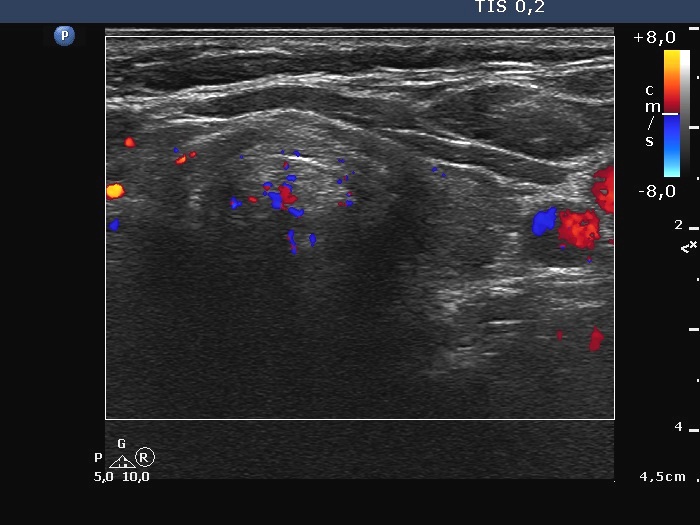

Left lobe, transverse scan, color Doppler mode. This lobe is avascular.